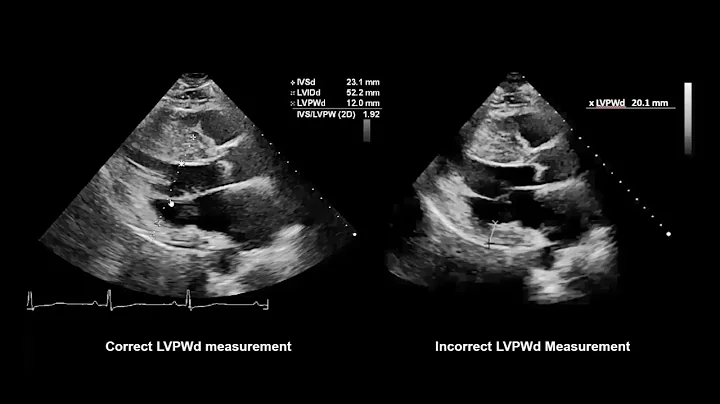

Lv M-mode Measurements #echocardiography #echo #cardiology #ultrasound #cardiachealth #hearthealth